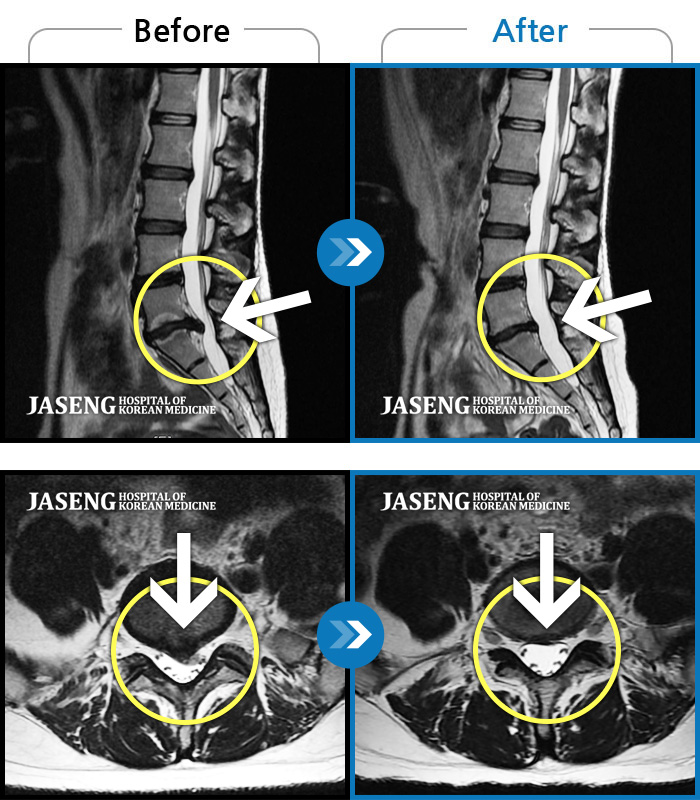

ȯںп Ǹ ǿ ԿǾ, ο ġ ۿ Ƿ ġḦ Ͻñ ٶϴ.